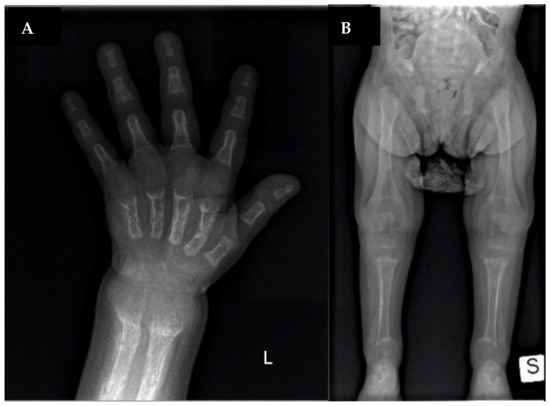

| Clinical features | Bone pain, osteomalacia ankle soreness, low back pain, fatigue, pseudofractures | Rachitic lesions at the wrists and knees, growth retardation | Genu valgum, decreased energy, moderately severe rickets | Rachitic rosary, metaphyseal widening, fraying and cupping of the ulna and the distal femur | Genu varum, growth retardation | Bone deformities, dental hypoplasia, frontal bossing, short stature, pectus carinatum, anterior bowing of both legs, pelvis retroversion | Bone deformities, dental hypoplasia, frontal bossing, short stature, pectus carinatum, anterior bowing of both legs | Genu varu, severe rickets, waddling gait | Rickets, short stature, pain in spine/hips/legs and difficulty in walking, kyphoscoliosis, proximal muscle weakness in all four limbs, and genu varus, deformity of bilateral lower limbs | None | Hypotonia, Rickets, growth retardation |